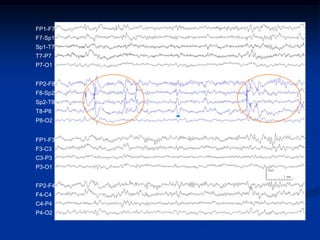

Descarga focal

eletrencefalograma

FP1-F7

F7-Sp1

Sp1-T7

T7-P7

P7-O1

FP2-F8

F8-Sp2

Sp2-T8

T8-P8

P8-O2

FP1-F3

F3-C3

C3-P3

P3-O1

FP2-F4

F4-C4

C4-P4

P4-O2